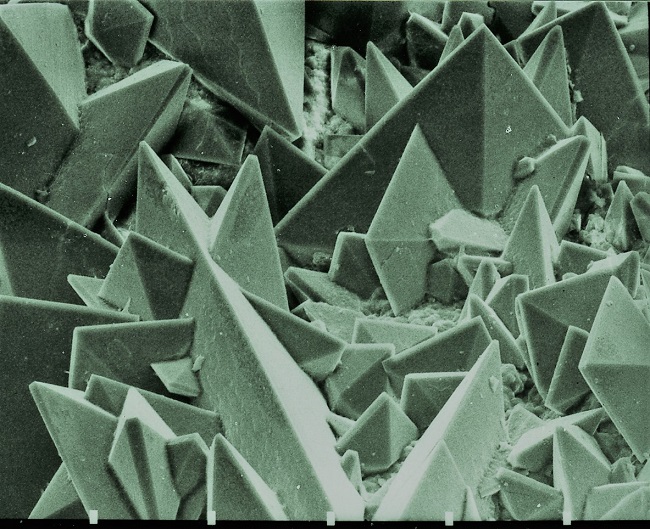

There is a truism in the sociology of occupational knowledge: “If all a doctor has is a hammer, then everything becomes a nail”. All modern medicine relies on overkill dosages of drugs or surgery as the standard of care (Jennifer Daniels, MD, The Lethal Dose, 2013). There are no drugs or surgery that can alleviate the symptoms of poisoning from a natural pesticide found in plant foods but also produced in the liver. With this professional void, treating oxalosis has mainly been left to nutritionists. So, if you ask a nutritionist about oxalates, you will get a predictable answer to reduce oxalates in your diet. This is insufficient because most oxalates are produced by poor metabolism in the liver. Oxalate is a natural pesticide found in plant foods, but also is internally produced mainly from fungus and vitamin C (see How Oxalates Ruin Your Health). Oxalosis manifests as a syndrome of three main symptoms: oxalate crystals in tissues and kidney; histamine, mucous attack in nasal passages; and pseudo-gout mainly from acidity and eating cooked meat.

First, I learned that calcium is needed as a co-valent chemical binder to oxalate before meals to eliminate oxalate through the bowel or oxalic acid through with urine through the kidney. Secondly, I learned that plant foods like spinach, almonds, chocolate, and soy and were loaded with toxic levels of oxalates, a natural pesticide that protects plants from insects, worms, and herbivores. I also learned that high doses of synthetic Vitamin D (10,000 mg/day as a steroid) without Vitamin K2, could also lead to kidney stones and oxalosis. An iron deficiency may come into the picture as discussed below.